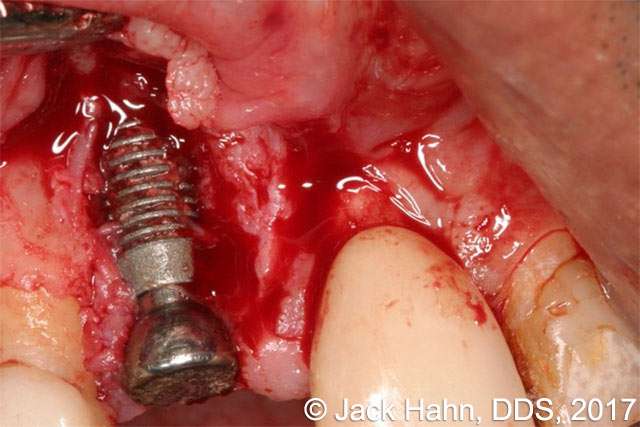

CASE #1 LightScalpel Laser Used to Remove Granulation Tissue After Debridement and Curettage of an Implant Site

After normal manual debridement and curettage of the implant site, the LightScalpel laser was used to remove additional granulation tissue. The ability to reduce bacterial load is due to the CO2 laser’s affinity for water and very high moisture content in bacteria. Treatment of the recipient bed with a CO2 laser decreases risk of infection and enables faster bone graft healing.